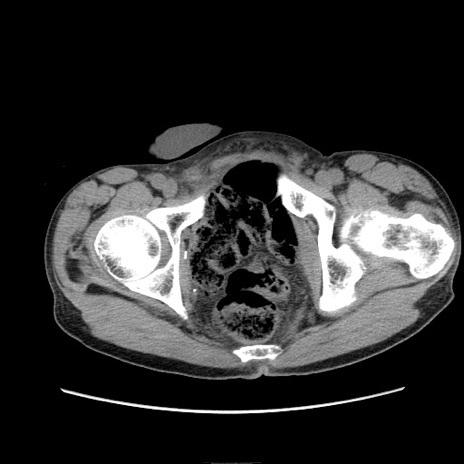

症例11(横断像)

【症例】 60歳代男性

【主訴】 下腹部痛

【現病歴】 本日夜中より下腹部痛の症状認め、受診。

【既往歴】 膀胱癌(膀胱全摘+尿管皮膚瘻術) 、胃癌術後

【身体所見】 BT 35.3℃、PR 58/min、BP 136/98mHg、腹部平坦、軟、腸蠕動音±、ストマ留置あり、左上腹部~正中部に圧痛あり、反跳痛なし。

【データ】WBC 5100、CRP0.01